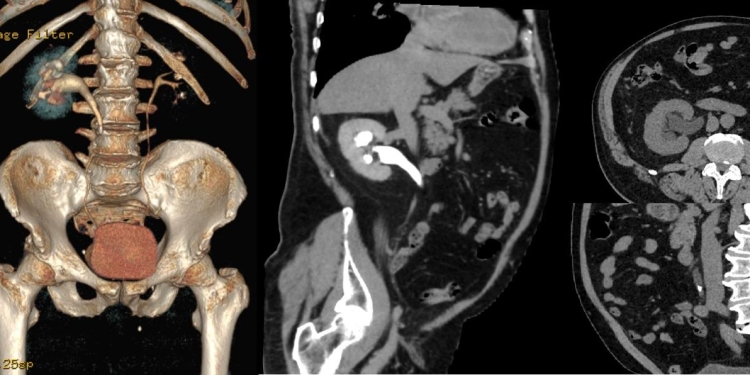

„URO-CT-ul este considerat o evaluare superioară față de urografia clasică, deoarece oferă imagini mai detaliate și poate detecta o gamă mai largă de afecțiuni. Investigația folosește o combinație de raze X pentru a genera imagini în secțiune ale rinichilor, ureterelor și vezicii urinare. Procedura este non invazivă, iar rezultatele se pot obține foarte repede, ceea ce permite începerea unui potențial tratament într-un interval de timp foarte scurt. Pentru a capta imagini și mai clare, se utilizează, de obicei, o substanță de contrast iodată, care este injectată în venă înaintea scanării”, a explicat asistentul Emil Stoicescu, Radiologie si imagistică medicală de la Spitalul de Boli Infecțioase „Victor Babeș” din Timișoara.

„Este important de menționat că, înainte de a efectua o tomografie computerizată urologică, se vor lua în considerare factorii individuali ai pacientului, inclusiv istoricul medical, simptomele, dar și alte investigații anterioare. Imaginile obținute prin URO-CT furnizează informații legate de extinderea și localizarea precisă a unei afecțiuni, ceea ce permite stabilirea unui plan terapeutic pentru fiecare pacient în parte. De exemplu, în cazul pietrelor la rinichi, dimensiunea și localizarea acestora pot influența decizia cu privire la intervenția chirurgicală sau la alte metode de tratament. De asemenea, cu ajutorul acestui screening poate fi apreciată si calculată densitatea calculului reno-urinar. Datorită capacității sale de a evidenția chiar și cele mai mici modificări ale țesuturilor și structurilor anatomice, URO-CT-ul poate contribui la detectarea precoce a afecțiunilor urologice”, a precizat Emil Stoicescu.